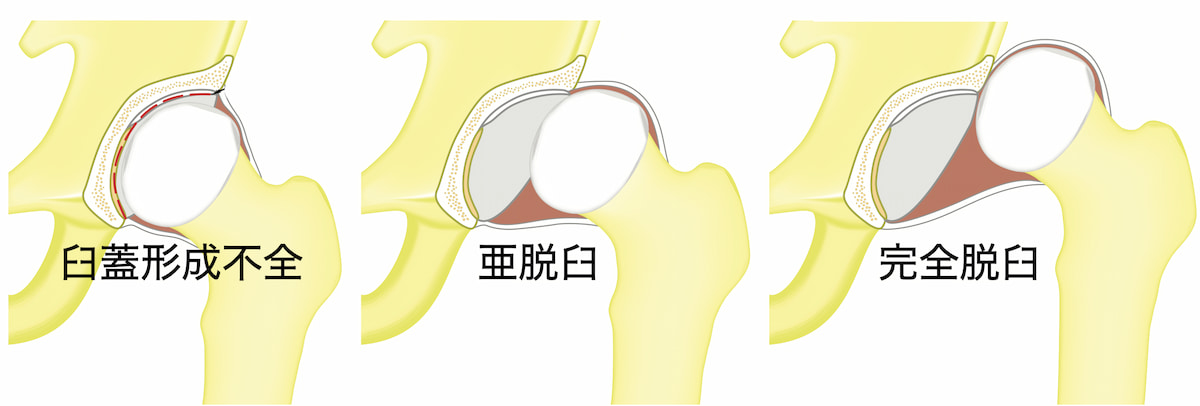

脱臼しやすい股関節で生まれてきた児が、間違った方法で育てられることによって、徐々に脱臼が進行します。出生時に脱臼していることは少ないので、最近は「先天性股関節脱臼」ではなく「発育性股関節形成不全」と呼ばれています。

発生率

脱臼しない育て方